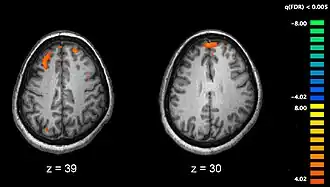

Phonological processing yields phonological codes (or representations) which are then used in speech processing to reach higher-level lexicon representations that are essential for auditory speech comprehension [6]. Strong empirical evidence shows the involvement of the posterior middle temporal lobe regions in accessing lexical and semantic information [6][8][11]. Lesion studies of the posterior temporal lobe have also supported this evidence. Elizabeth Bates and her colleagues studied 101 left-hemisphere aphasic patients and found that lesions to the middle temporal gyrus (MTG) most accurately predicted auditory comprehension deficits, with a significant deficit also observed with dorsolateral prefrontal cortical lesions. Whereas, lesions to the insula and arcuate/superior longitudinal fasciculus affected verbal fluency the most [12]. Functional magnetic resonance imaging studies (see Figure 3 for an example of an fMRI scan) have further implicated the posterior middle temporal lobe regions in semantic processing. In a semantic decision task in research conducted by Jeffrey Binder and colleagues, activations were found in both sides of the STS and almost all of the MTG in the left hemisphere. They also found that this activation spread ventrally across the inferior temporal gyrus (ITG). The authors found further activations in the angular gyrus, anterior and posterior cingulated gyrus, portions of the precuneus, retrosplenial cortex, and cinglulate isthmus in the left hemisphere; as well as subcortical activations in the anterior thalamus in the left hemisphere. [11]. Many positron emission tomography (PET) studies (see Figure 4 for an example of a PET scan) examined the activated areas in response to semantic processing. They too found left lateralized non-STG temporparietal regions; including the MTG, inferior temporal gyrus (ITG), and the angular gyrus [13] [14][15].